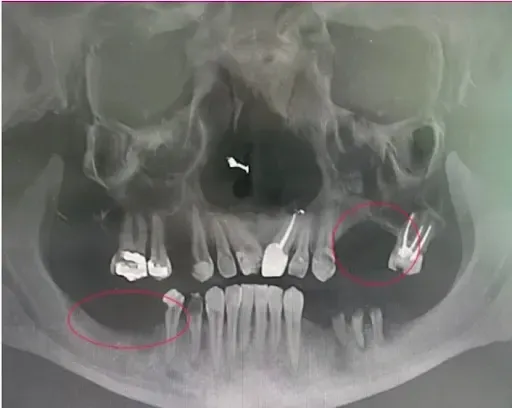

If you’ve already received your CT scan you can see infection by looking at dark holes where there should be bone. You can also very easily see where the bone has disappeared because a tooth or several teeth were pulled.

The scan below shows you a mouth with severe infection. The infection is circled. In fact, there was so much infection on the upper jaw which had been there for so long, this person was no longer a candidate for dental implant treatment and was confined to a denture.